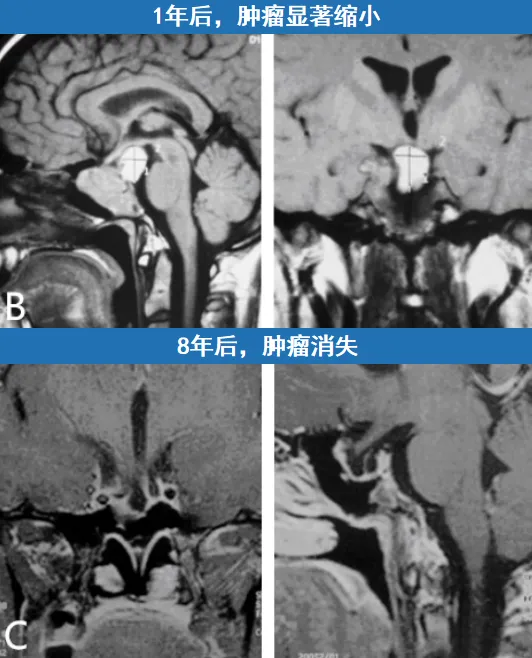

幸运的是,该治疗方案对小A产生了显著效果。药物治疗一段时间后,肿瘤体积迅速缩小。一年后的复查磁共振显示,肿瘤已大幅缩小,小A的视力障碍也完全消失。最终,经过长达八年的药物治疗后,复查证实小A颅内的肿瘤已完全消失,且其他相关激素水平均未受到不良影响。